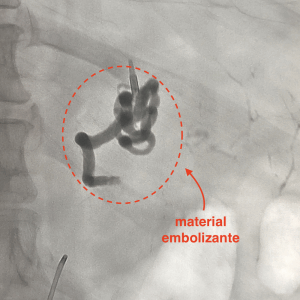

A embolização é realizada durante um procedimento de arteriografia ou flebografia. Trata-se de um procedimento moderno, com utilização de recursos tecnológicos que permitem que a técnica seja realizada com apenas um pequeno furinho na virilha ou no punho, utilizando-se na grande maioria das vezes apenas anestesia local.

Um pequeno cateter é introduzido por meio desse furinho, de forma indolor, e então navega por dentro das artérias até chegar ao ponto onde esteja ocorrendo o sangramento.

Em seguida, o médico Radiologista Intervencionista provoca a oclusão dessas artérias (embolização), a fim de obstruir o seu fluxo sanguíneo e, consequentemente, o sangramento. Ao final do procedimento retiram-se os cateteres e é feito um curativo no local do furinho.